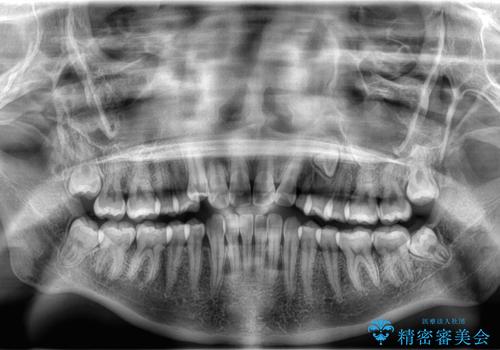

左側犬歯が埋伏していましたが、第一小臼歯(4番目の歯)を抜歯したことでできたスペースに牽引し、右側の飛び出した八重歯を含め、歯全体を整列することができ患者様も満足していただきました。

犬歯牽引を行うかはCTを撮影し判断を行なっています。